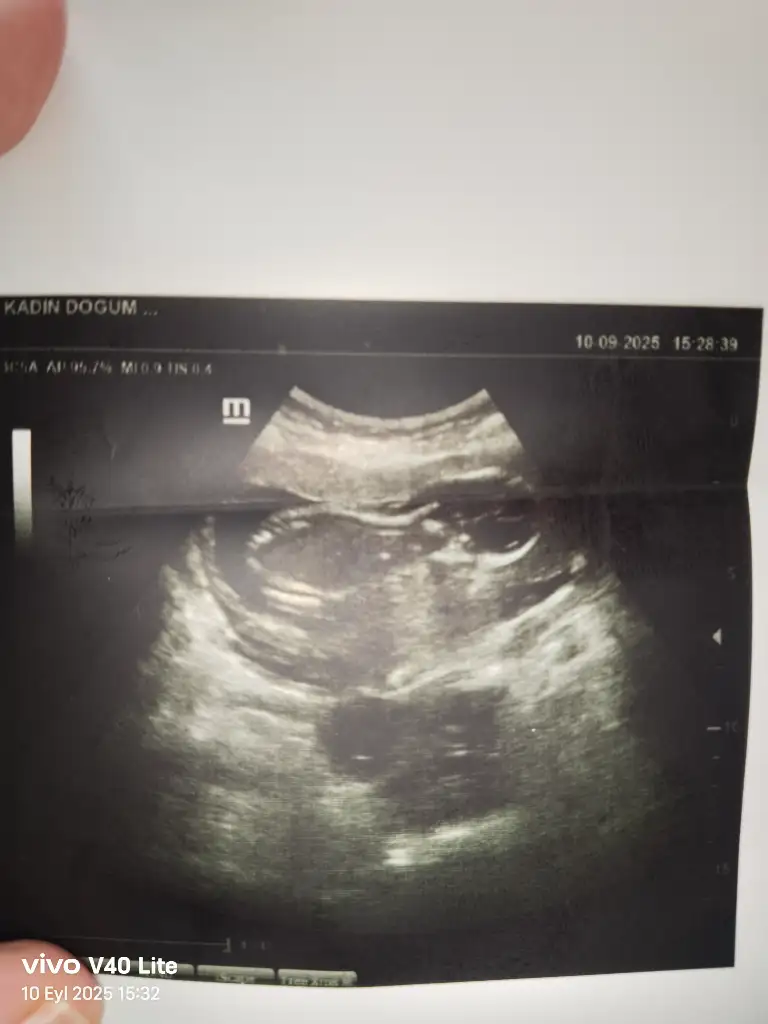

Banada tahminde bulunabilir misiniz? Kendi doktorum erkeğe benziyor başka bir doktor kıza benzettiği söyledi

Dojtorunuz ölçüm çizgisini hep cinsiyet kısmına denk getiriyor, yine aynı olmuş 🤦🏻‍♀